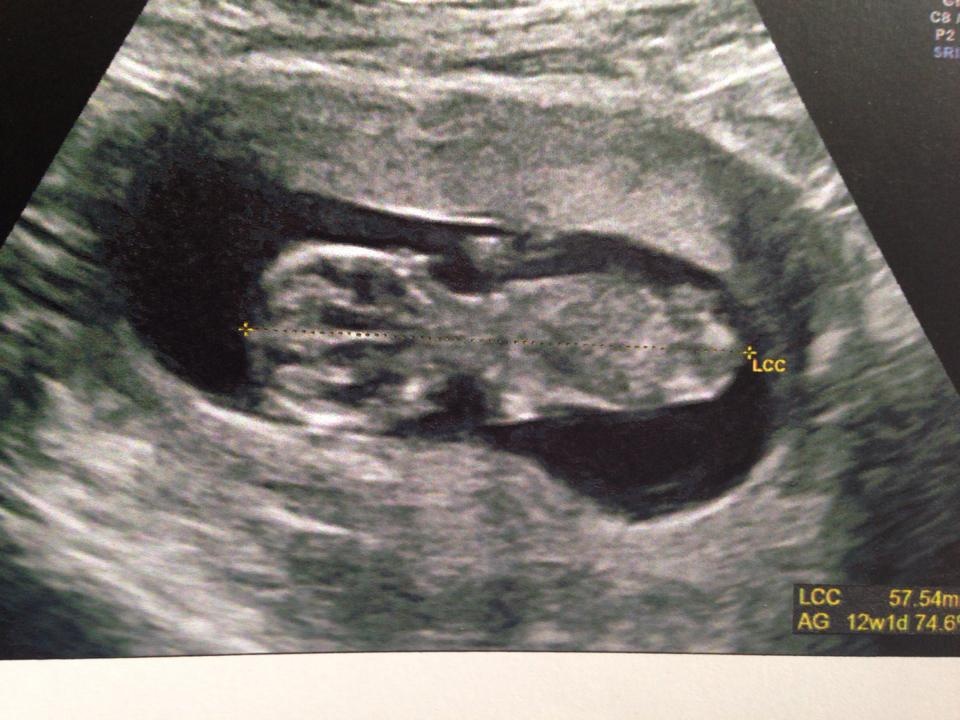

alors voila ma crevette qui fait 57 mm bébé est de dos il ne s'est pas laissé voir du coup je connaitrait le sexe a la prochaine echo ...... le 1er avril mouahahha

Pièces jointes

• bb2.jpg

bb2.jpg

129.8 KB · Affichages: 72